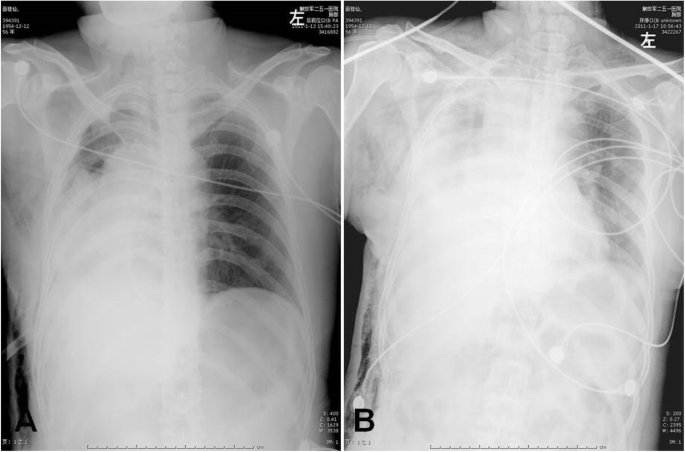

A 52-year-old woman with a 3 month’s history of cough and hemoptysis consulted a nearby clinic. Chest X-ray showed atelectasis of the right upper lobe caused by locally advanced lung cancer with mediastinal invasion. Bronchoscopic biopsy showed squamous cell carcinoma. Chest computed tomorgraphy (CT) showed atelectasis of right upper lobe tumor invasion into the right main pulmonary artery. The SVC was compressed and narrowed but remained patent (Fig. 1). No significantly enlarged mediastinal lymph nodes were seen. Bronchoscopy revealed an exposed tumor in the right upper bronchus which completely obstructed the lumen. Brain and abdominal CT, and bone scintigraphy revealed no signs of distant metastases. On the basis of these findings, the tumor was evaluated to be resectable by intrapericardial pneumonectomy. The surgery was performed through a right thoractomy. The pericardial was opened from SVC to the level of right upper pulmonary vein 2 cm posterior and parallel to the phrenic nerve. The SVC was isolated from the atrium to the brachiocephalic trunk, which involved SVC denudation at the point of its connection with pericardium. Then the right pulmonary artery was dissected and ligated between the ascending aorta and the SVC. The right upper pulmonary vein was ligated intrapericardially. The right lower pulmonary vein was dissected and ligated outside of the pericardium. Finally the right main bronchus was manipulated using a stapler to complete the right pneumonectomy. No direct tumor invasion into the SVC was detected. The lower part of pericardium was closed interruptedly and the upper defect was left open. The chest was drained using an intercostals tube that was kept clamped and released for half an hour the next morning. The patient was transferred postoperatively to Intensive Care Unit, and the tracheal tube was withdrawn 2 h after operation. About 18 h after operation, the patient was transferred to an ordinary room. Immediately after a short period of hard coughing, the patient developed tachycardia arrhythmias, hypotension, followed by loss of consciousness. After resuscitation, the patient was conscious but developed cyanosis of the SVC drainage area, uropenia, and hypotension (80/30 mmHg). She felt more comfortable in the right decubitus position. Emergency bedside-echocardiography showed that the SVC was obstructed due to thrombus formation. Cardiac herniation into the right pneumonectomy space was detected on repeated chest radiography which showed a shift of the heart into right hemithorax (Fig. 2). Rethoracotomy was performed on the second day after the intrapericardial pneumonectomy. At operation it was found that the heart had rotated into the right hemithorax along the axis of the vena cava, and the SVC was strangulated. The heart was placed back into its normal position. The pericardium was torn from its initial incision to cardiac apex for about 8 cm and this was repaired using a Gore Tex patch. About 5 min after the heart was returned to its normal position, the syndrome of SVC disappeared. The postoperative course was uneventful. The patient has been followed up as tumor-free for more than 3 years.

A majority of cardiac herniation occurs within 24 h of surgery and 75% of the events occur intraoperativley [6]. Although there is a report of cardiac herniation occurring 6 months after right pneumonectomy, late herniation occurring 24 h after surgery is rare because of rapid formation of adhesions between the heart and the pericardium [7]. In our case, cardiac herniation occurred about 18 h after surgery. Considering the fact that cardiac herniation is a life-threatening condition with mortality of 50% in recognized cases and 100% in undiagnosed cases [3], early diagnoses is pivotal. The symptoms of cardiac herniation are related to location of pericardial defect created by cardiac dislocation. On the right side, obstructive shock includes kinking or torsion of both SVC and the inferior vena cava with subsequent reduction of cardiac filling causing a decrease in systemic blood pressure, a dramatic increase of central venous pressure and a sudden onset of tachycardia [8]. On the left side, cardiac herniation produces dysrhythmia and acute myocardial ischemia, which can compress or strangulate the ventricular wall due to the pericardial edge leading to hypotension, ventricular fibrillation and infarction [9]. With right cardiac herniation, the characteristic radiologic findings on chest radiograph include: displacement of the heart from the midline with cardiac apex located on the right, an abnormal cardiac contour with a globular right cardiac border protruding into the right chest [10,11,12], a notch on the side of cardiac vascular pedicle, a clockwise rotation of the Swan Ganz catheter or a kink in the central line at the level of brachiocephalic venous junction [13], and a change in the position of the chest tube. With left cardiac herniation, the classic radiologic findings include: a hemispherical shape of the left heart border, an incisura between the great vessels and the herniated left cardiac chambers, a change in the position of the chest tube, and an empty pericardial sac. Transthoracic echocardiography could also provide an accurate diagnosis [14]. However, in this case, the transthoracic echocardiography did not provide much information other than a SVC obstruction.